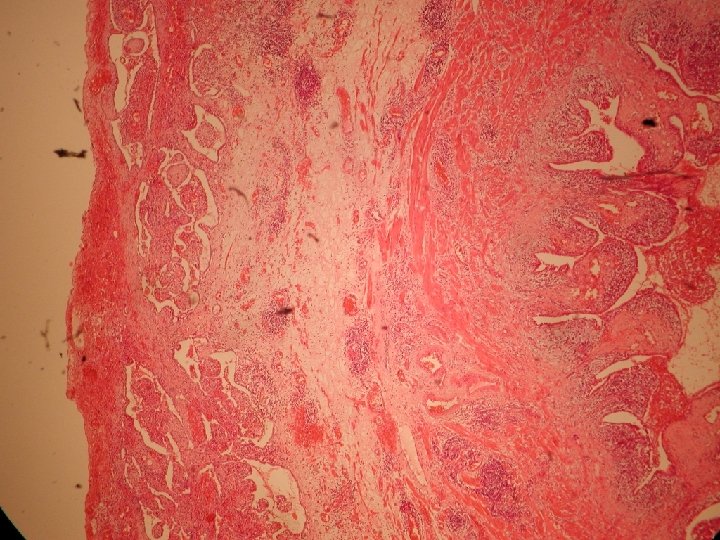

Sklíčkový seminár SD-IAP, 2014 prípad č. 501 Ondič O. , Bioptická laboratoř, Plzeň

Klinické údaje • Žena, vek 48 rokov • Operovaná pre „zápalový tumor adnex“